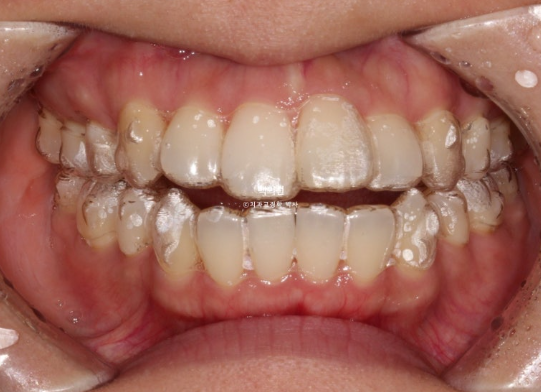

23년 1월 교정을 위해 내원한 30대 환자분입니다.

고치고 싶은 것은 돌출입이였고 장치는 인비절라인 선택하셨습니다.

23.01

앞니 덧니가 보입니다.

중심선이 약 2mm 어긋나 있습니다.

앞니 뻗침은 심한 편 입니다.